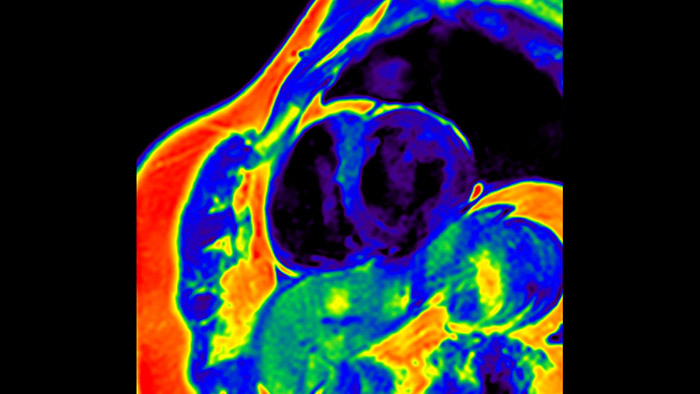

Today's diagnostics often cannot detect heart dysfunction until symptoms occur. MyoStrain utilises segmental strain to measure 48 segments of the heart and provides physicians with a unique diagnostic tool to help identify regional dysfunction before the heart as a whole is affected.

IntelliSpace Portal MR Caas5,6 Strain7 assists in patient diagnosis and monitoring by providing global strain parameters such as global longitudinal strain (GLS), global circumferential strain (GCS), and global radial strain (GRS), using short and long axis MR images, as well as describing the myocardium deformation- such as shortening, thickening, and lengthening during the cardiac cycle.